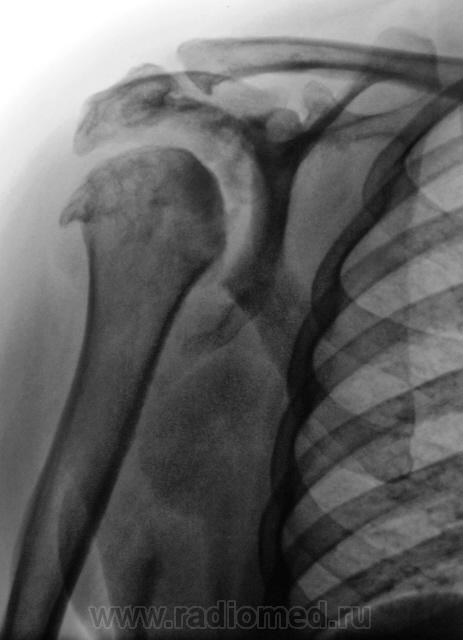

Да патология весьма интересная. Мы долго ломали голову взвешивая все "ЗА", проводя диф. диагностику между сирингомиелией и волчанкой.

Но данный случай имеет и другой, а именно, "коллегиальный аспект". Пациентка обратилась к хирургу по поводу болей в плечевом суставе. Коллега хирург не желая вникать в подробности, сразу-же выписал направление на рентгенографию плечевого сустава, выставил формальный диагноз - "деформирующий артроз". Пациентка исчезла, где-то на месяц, но затем явилась за заключением, так как "обновляет группу". Каково-же было удивление, когда при анализе амбулаторной карты, было выявлено "море исследований", проведенных ранее, включая КТ, МРТ и т.д. и т.п., и диагноз "Сирингомиелия" проходил "красной нитью".

А для волчанки, такая картина, не характерна.